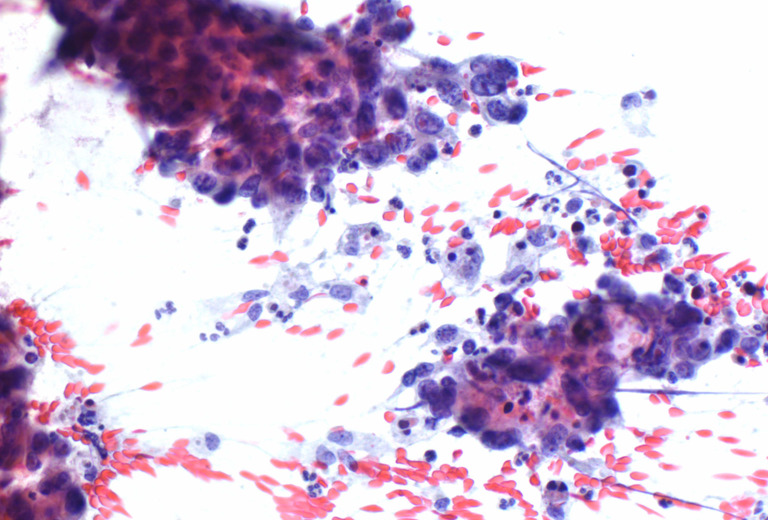

Pathologie Medica Enge is one of Switzerland’s market-leading pathology institutes and offers morphological investigations for tissue and cell samples from all organ systems. Our team covers the entire spectrum of pathology and meets the highest diagnostics requirements thanks to state-of-the-art processes.